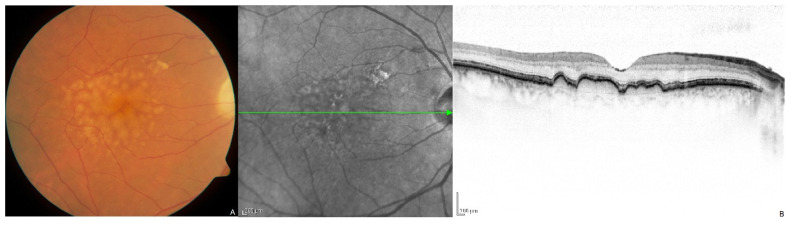

年龄相关性黄斑变性 (AMD) 的特征是黄斑区视网膜色素上皮 (RPE)

和/或视网膜下沉积物(分别称为视网膜小疣或网状假性视网膜小疣)的积聚,通常始于 70

岁以后(图1

多种病理生理机制已被证明与年龄相关性黄斑变性 (AMD) 的发展有关,所有这些机制都与 RPE 功能障碍和退化有关。氧化应激似乎发挥了重要作用 。吸烟——增加氧化负荷并削弱抗氧化防御机制 ——因此被认为是影响年龄相关性黄斑变性 (AMD) 发展的最显著的可改变危险因素 。相反,增加饮食和补充抗氧化维生素和矿物质的摄入量是唯一被证明可以减缓疾病进展到晚期的干预措施之一 。随着年龄增长,累积的氧化损伤可能导致脉络膜毛细血管结构退化,从而导致流向 RPE 和光感受器的血流减少 。血液循环受损会降低脂质和细胞副产物的清除率,这些脂质和细胞副产物会积聚形成视网膜黄斑硬化症。反过来,脂质积聚可诱导细胞外基质 (ECM) 重塑并刺激炎症反应。这些致病过程之间复杂的相互作用 最终导致疾病进展为组织萎缩或黄斑新生血管形成(MNV,以前称为脉络膜新生血管形成 )。这两个终点代表了晚期年龄相关性黄斑变性 (AMD) 的两种主要形式:地图状萎缩 (GA,传统上称为“干性” AMD)和新生血管性 AMD(传统上称为“湿性” AMD)。然而,光学相干断层扫描 (OCT) 血管造影的出现使得非渗出性新生血管形成病例更容易识别,模糊了这些传统类别之间的区别 。